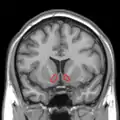

Approximate location of the nucleus accumbens in the brain